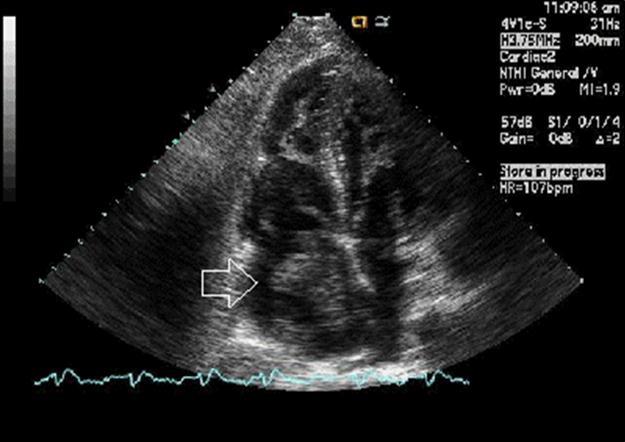

Echocardiogram shows: 1. Severely decreased LV ejection fraction. 2. Large, mobile thrombus in the right atrial cavity (Figure 1). 3. Moderately dilated right atrium. 4. Mild aortic regurgitation. 5. Mild concentric left ventricular hypertrophy. 6. The left ventricular size is mild to moderately increased. 7. Mild thickening of the anterior and posterior mitral valve leaflets. 8. Ischemic cardiomyopathy. 9. Mild aortic valve sclerosis without stenosis. 10. Mild mitral valve regurgitation. 11. Mildly elevated pulmonary artery systolic pressure. 12. Moderately enlarged right ventricle. 13. Moderately reduced RV systolic function.

Figure 1.Echographic image of Case 1 of the large, mobile thrombus in the right atrial cavity.